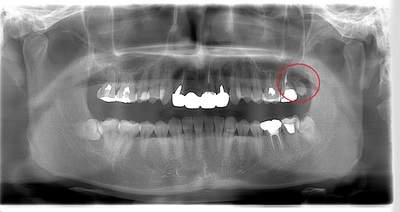

左上の親知らずが大きな虫歯になっていた症例

- 口腔内写真

- 抜歯前写真(レントゲン、CT等)

- 抜去歯の写真

| 年齢 | 30代・女性 |

|---|---|

| 主訴 | 虫歯の治療をしたい |

| 治療期間 | 1ヶ月 |

| 費用 | 約7,000円(保険治療内) |

| 治療方針 | 左上の親知らずをみてみると虫歯になっており、真っ黒になっていました。 そのため、虫歯治療ではなく、抜歯を行うことにしました。 |

| 抜歯内容 | 歯のクリーニング後、親知らずを抜いていきました。 |

| 特記事項 | 抜いた後は血圧が上がるようなこと(飲酒、運動、湯船に浸かる、マッサージ)などは行わないようにお願いします。 またドライソケット防止のために、抜いた箇所は触らないように、うがいも優しくするようにしてください。 歯ぐきに炎症がある場合は麻酔が効きづらくなりますので、炎症が治まってからの抜歯になります。 |